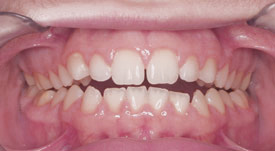

Crossbite

Crowding Front

Crowding Lower

Crowding Upper

Midlines

Narrow Upper Arch

Openbite

Overbite Front

Overbite Side

Protrusion

Spacing

Underbite